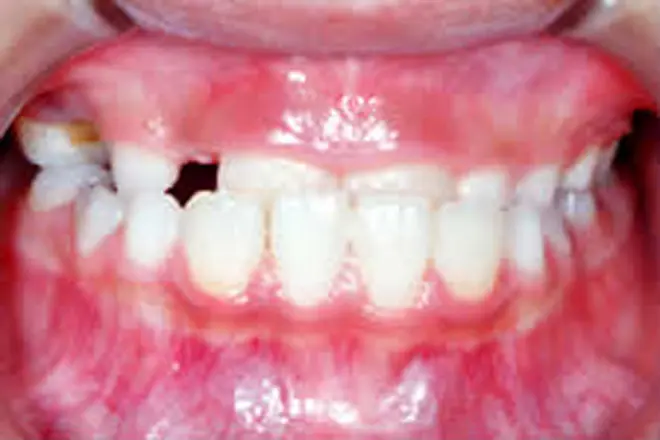

子どもの矯正 治療例1

前歯が出ている状態で反対に噛んでいる場合、自然に治ることはありません。

また、10歳くらいまでは上顎が盛んに成長する時期で、このままだと上顎の成長に支障が出る可能性があります。そこで、前歯の矯正治療を開始しました。

治療期間は6ヵ月で治療完了です。反対咬合が治りました。

この後は数ヵ月に一度、永久歯が生えそろうのを経過観察していきます。

| 患者さまの年齢・性別 | 8歳・女性 |

| 治療期間 | 6ヵ月 |

| 治療費(税込) | 330,000円 |

| 主訴 | 前歯が反対に噛んでいる |

| 診断名・主な症状 | 反対咬合 |

| 治療に用いた主な装置 | 表側矯正装置 |

前歯(永久歯)が萌出した状態で反対に咬んでいる場合、自然に治ることはありません。また10歳くらいまでは上顎の骨が盛んに成長する時期であり、この状態では上顎の成長が充分に得られない可能性があるため、早めの治療が必要になります。 |

| 抜歯部位 | 非抜歯 |